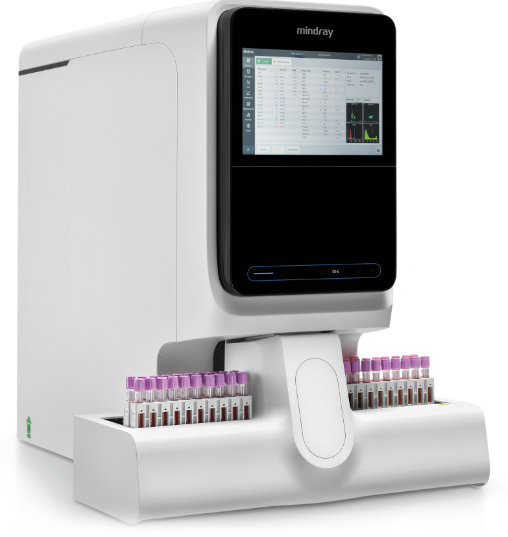

BC-7600 Series

BC-7600 Series Auto Hematology Analyzers provide comprehensive solutions for complete blood count (CBC), differential white blood cell count (DIFF), hematological malignant cells, low-value WBC/PLT, PLT clumps, etc. They also support the analysis of body fluids.

BC-7600 Series adopts SF-Cube principal, which has a good correlation with other Series for cross-checking of patient results.